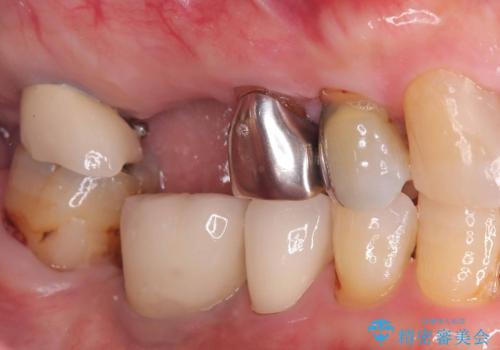

- 虫歯が原因で歯が欠けていました。昔詰めた保険の材料(CR)が劣化しその下が虫歯になっている状態でした。

色々な箇所にCR(保険の材料)を詰めてあったので、CRと虫歯を全部除去した後、オールセラミッククラウンで治療を行いました。

古いCR(保険治療で使用されるプラスチック)を除去すると残りの歯質が薄いため、破折抵抗を考慮しオールセラミッククラウンで治療を行いました。